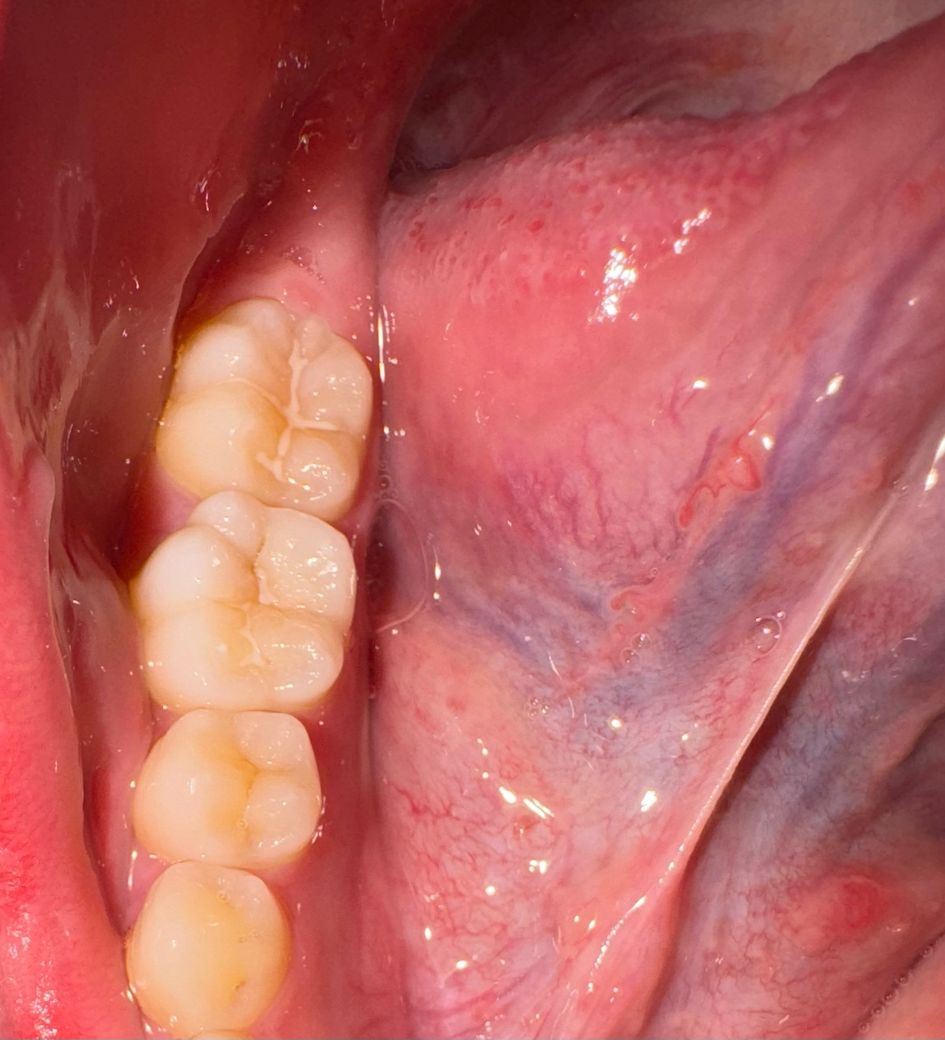

• 2번 째 사진

일부 떨어진 부위도 보이고 착색이 아닌 충치가 나타난 것으로 보여집니다. 현재 사진으로 보아서는 그 충치가 커 보이지 않으며 간단한 레진 등으로 치료가 가능할 것으로 보입니다. 더 커지기 전에 충치 부위를 제거하고 레진 등으로 치료하는 것을 권해드립니다.

사진만으로는 약간 애매한 부분이 있어 해당 부분은 치과 내원하셔서 검진 받으시는게 좋아보입니다. 변연 일부 변색되며 보이는 부분도 있는 것 같으며 우식도 일부 있을 가능성도 있어 보이기도합니다. 자세한건 검진 꼭 받아보시기를 권유드립니다.

일부실란트는 떨어져 나간 것 같고 충치로도 보입니다 치과가서 정확히 탐침으로 긁으며 검사해봐야합니다